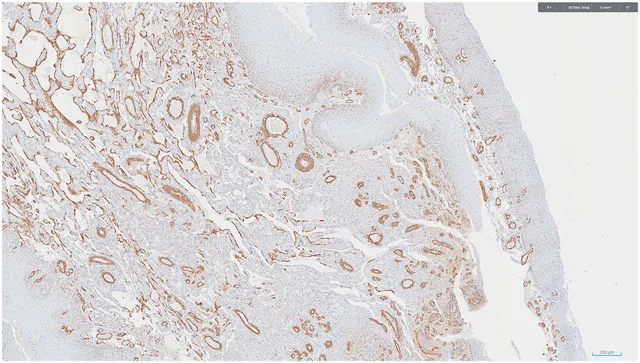

9 ACTINA

- TÉCNICAS DE INMUNOHISTOQUÍMICA: WT1, CD31, CD34, HHV-8: positivas.

Diagnóstico: SARCOMA DE KAPOSI, con intenso artefacto de cauterio en la muestra remitida.

- El diagnóstico definitivo de sarcoma de Kaposi (SK) se basa en la identificación del herpesvirus humano 8 (HHV-8) PMID: 39649864